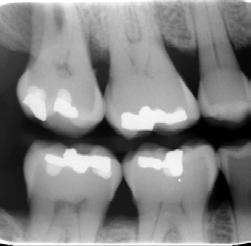

Fokus på bitewing bilden. Röntgen för tandhygienister

Tandhygienistens kompetens innefattar att självständigt undersöka patienter med avseende på karies och parodontit. Det är därför viktigt att förstå betydelsen av detektorplacering, projektion, exponering, eventuell bildbehandling och bildtolkning. Här går vi igenom bitewing bildens betydelse som ett hjälpmedel för ett lyckat resultat och även ökad kunskap om förändringar som kan ses på bilden utöver karies och parodontit.